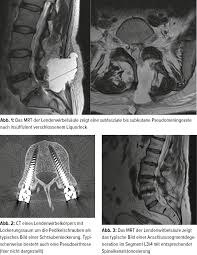

Komplikationen In Der Wirbelsaulenchirurgie Wie Vermeiden Wie Behandeln Orthopadie Traumatologie Universimed Medizin Im Fokus